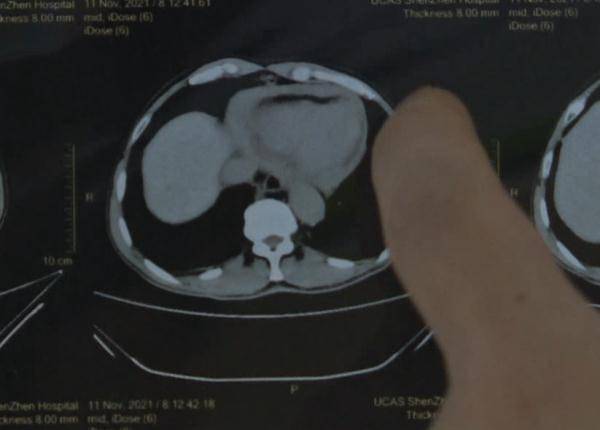

“患者升主动脉瘤已经扩张 , 同时有心包积液 , 预示他已经有破裂的前兆 。 ”

【手术|男子胸痛两年没重视,差点被体内“定时炸弹”夺命】正常人的升主动脉在2至3厘米

但刘先生已达到6厘米

“就像吹气球 , 随时可能破裂 。 ”